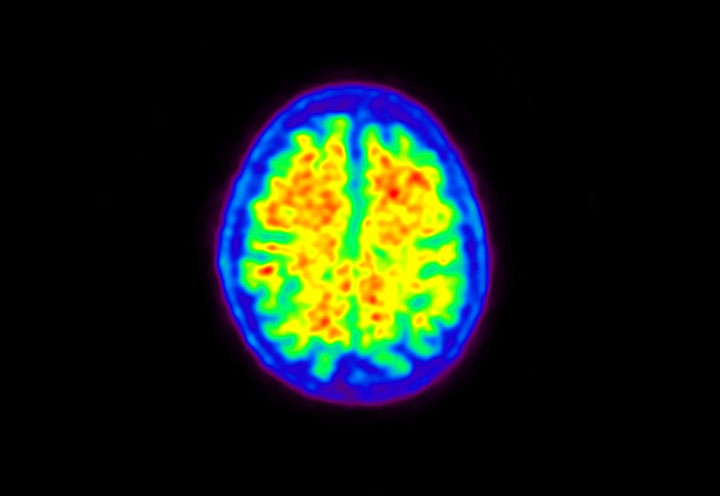

Head / Case5 : Amyloid

Courtesy : Kindai University Hospital

- Imaging protocol

- Injected dose: 4.27 MBq/kg, 18F-Flutemetamol

- Uptake time: 99 minutes

- Scan time: 20 minutes